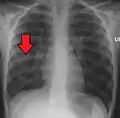

A chest x-ray of a patient with severe viral pneumonia due to SARS